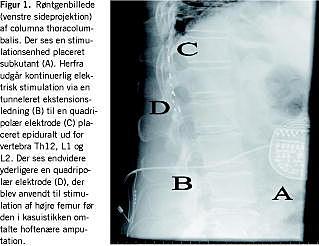

I 1999 havde patienten et faldtraume og pådrog sig et sår på amputationsstumpen. En infektion nødvendiggjorde en hoftenær amputation af femur med en efterfølgende forværring af fantom- og stumpsmerterne. På grund af ændret smertelokalisation blev en ny elektrode til SCS implanteret med godt resultat (Figur 1). Forbruget af opioider kunne nedtrappes til et minimum og gabapentin blev seponeret. Effekten af SCS var stabil frem til efteråret 2004, hvor stimulationsenhedens strømkapacitet var opbrugt, og patientens forbrug af ketomibedon hurtigt var blevet øget til 75 mg dagligt. Der blev efterfølgende foretaget en ukompliceret udskiftning af stimulationsenheden, og medicinforbruget normaliseres. Ved en ambulant kontrol 12 måneder senere var patienten fortsat tilfredsstillende smertelindret.